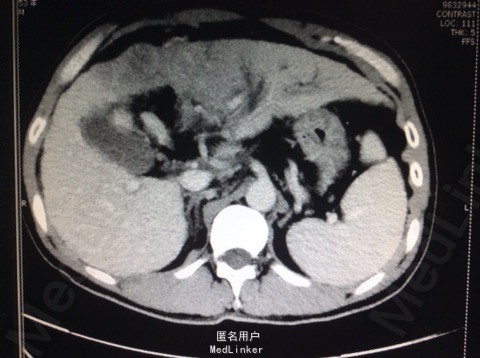

患者男,53岁。 主诉:上腹胀痛1月余。 现病史:患者于一月前无明显诱因出现上腹胀痛,为持续性胀痛,以剑突下为主,向右肩部放射,无恶心、呕吐等不适,腹痛与进食无明显关系。当地医院行CT 检查提示"肝脏右叶大片低密度影”,诊断为"肝癌可能",给予护肝等治疗,腹胀无明显好转。 起病以来,饮食欠佳,大便正常,小便色黄,体重下降3kg,体力下降。 既往史:乙型病毒性肝炎10余年。 查体:体温36.2℃,脉搏104次/分,呼吸20次/分,血压104/74mmHg,剑突下压痛,肝剑突下2横指。

辅助检查: 2013-10-16市中心医院CT提示,肝脏右叶大片低密度影 2013-10-22市中心医院胃镜1、中度食管静脉曲张,2、慢性浅表性胃炎;直肠 炎。 肝功能谷丙转氨酶22U/L,谷草转氨酶49U/L,白蛋白33.5g/L。总胆红素23.1 umo1/L,直接胆红素8.20 umo1/L。乙肝病毒(HBV-DNA) 3.13×103。 腹部超声:1.肝内巨大实质性肿块并肝左叶胆管扩张,2.肝硬化、脾肿大。